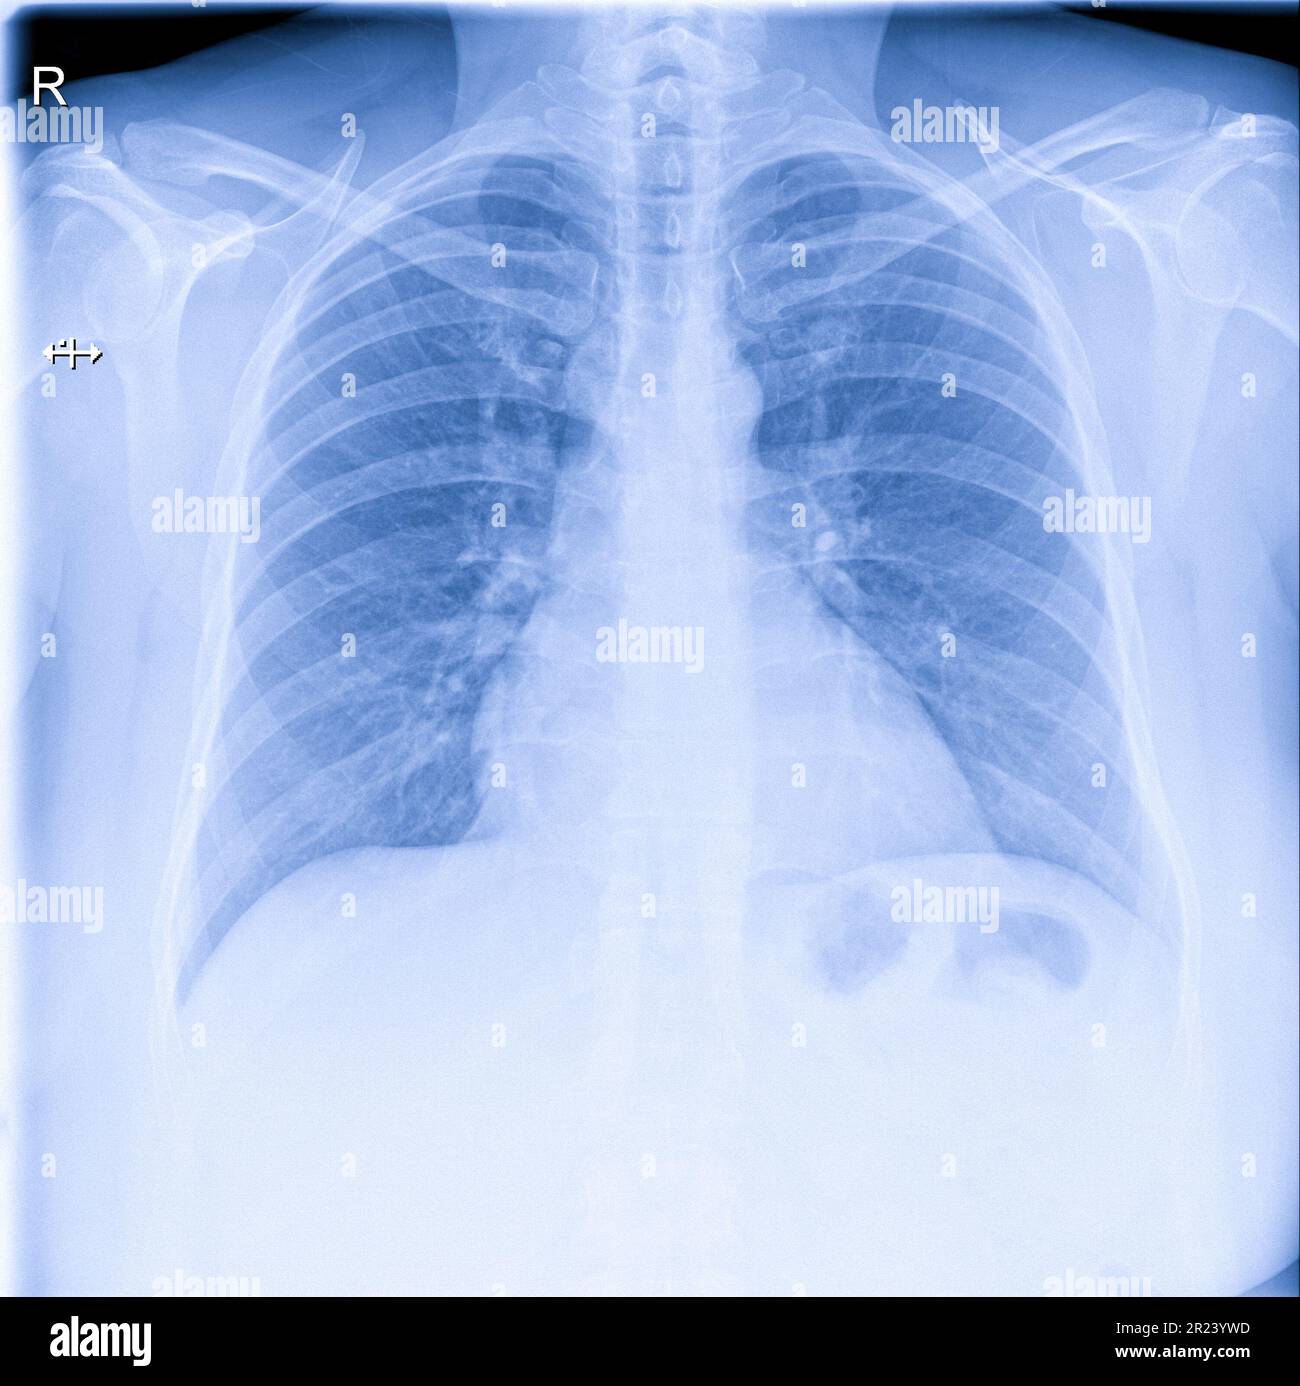

XRay Image Of Human Chest For A Medical Diagnosis Imagen de archivo Chest X Ray Clinical Diagnosis  A bad or persistent cough. Many cxr appearances may be recognizable immediately as indicating a.  19 rows  according to most clinical guidelines globally, the supposed gold standard tool for diagnosing pneumonia is a. Physicians use the examination to help diagnose or monitor treatment for conditions such as: Chest X Ray Clinical Diagnosis.